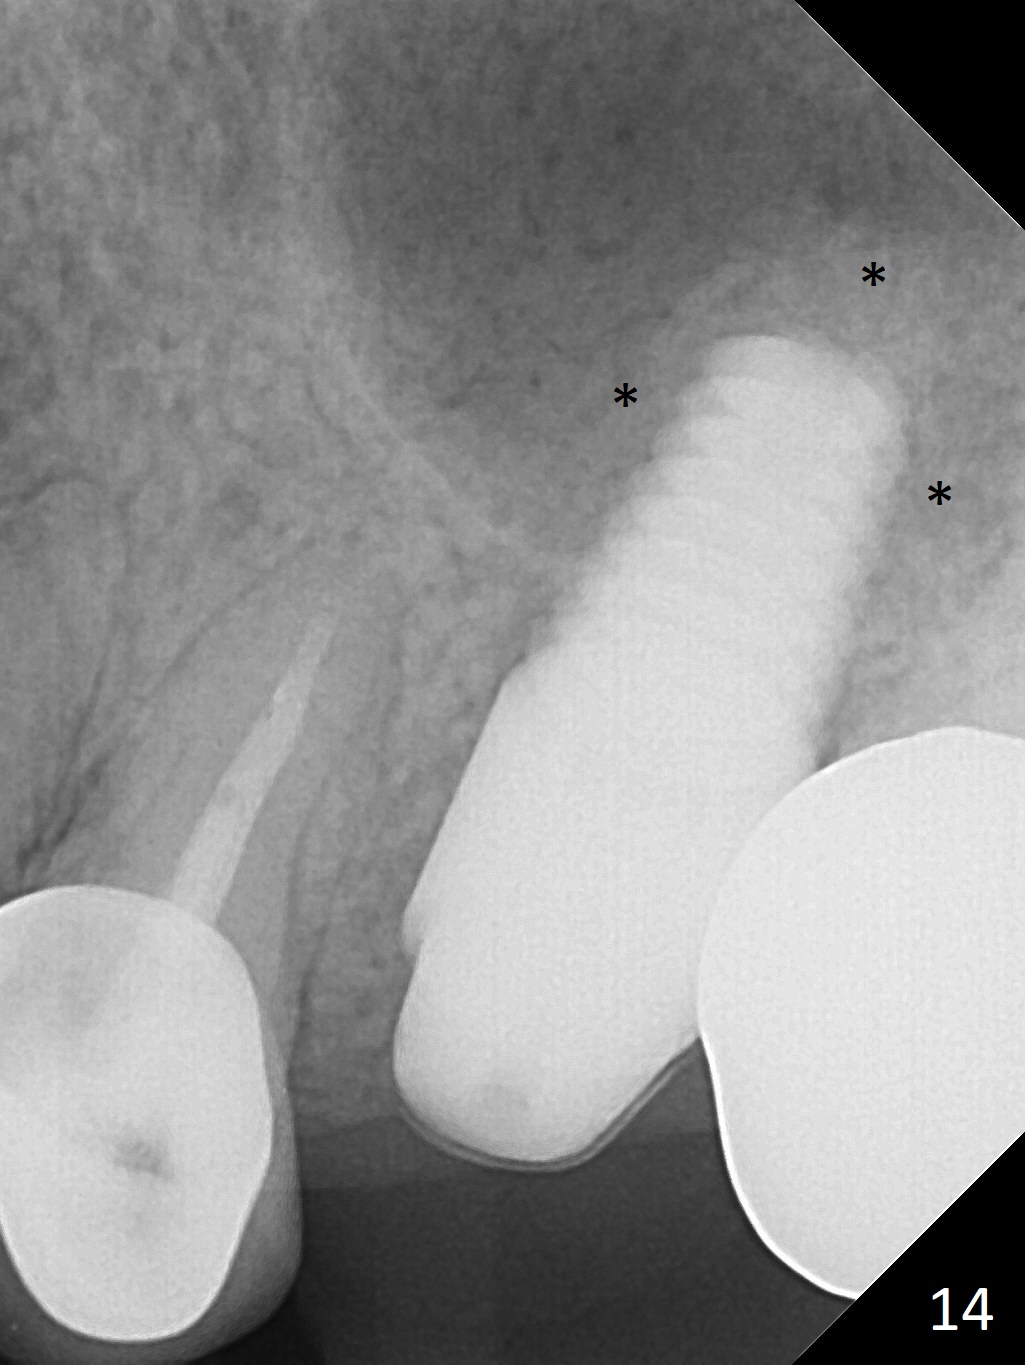

The patient is doing well 9 days postop. The immediate provisional is loose and over-sized. It is removed for trimming and reline; the socket and bone graft (Fig.8 *) are healing. It appears that an angled abutment is required next time of provisional revision. When an angled abutment is being placed 23 days postop (Fig.9), it appears to wiggle the implant due to its long leverage. Instead a healing abutment is placed. The implant is unstable 4.5 months postop with seemingly excessive bone-implant gap (Fig.10 <). The 5.5x9 mm implant is removed. A 5x17 mm tap is used to change the trajectory and sinus lift, followed by 6x17 one (Fig.11). Finally a 6x14 mm tissue-level implant is placed with insertion torque > 50 Ncm (Fig.12; vs. <20 Ncm (Fig.7,10)) and improved trajectory. An immediate provisional is fabricated to prevent the mesial drifting of the tooth #15 (Fig.13 P (*: occlusal clearance)). By using the taps and placing the longer implant, the sinus lift is more obvious (compare Fig.10 and 12 (*)). Sinus lift remains evident 3.5 months postop (Fig.14) with apparently osteointegration (Fig.15).